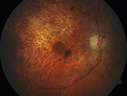

Concentric Geographic Atrophy - 76 year old man364 viewsGradual vision loss, worse at night. VA 20/40 OU.     (0 votes)

76 year old man The patient has noticed that his vision is getting worse at night. The vision loss has come on gradually. He notices that his vision in low lighting is poor and at night with oncoming headlights.

VA OD: Dcc20/40-1 NscJ7

VA OS: Dcc20/40-1 NscJ7

IOP: TP: OD:17 OS:18 Time:12:01 PM